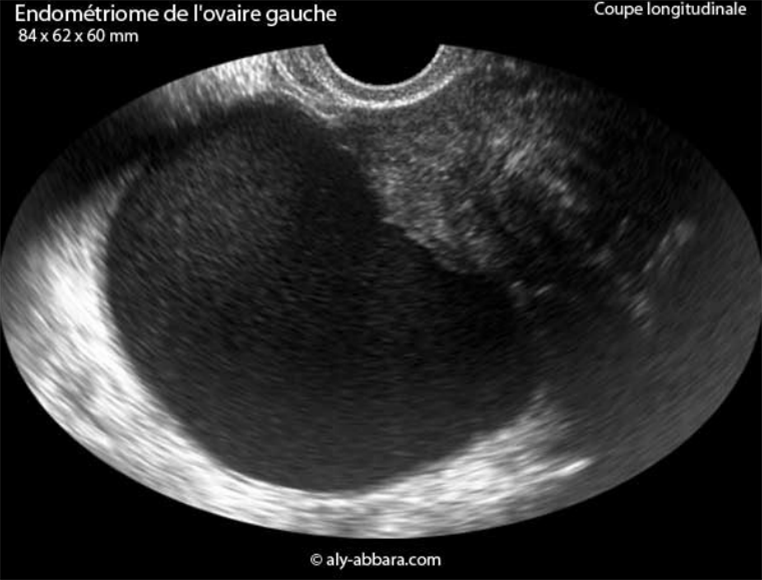

Luckily during my hospital visit my new gynaecologist agreed to surgery on the cyst on my left ovary. However, she wants to be certain that the lesions aren't wider spread (my rectum was mentioned eek). To do this I need a pelvic MRI.

As for "plan blanc" she said she wasn't scheduling anything before the end of September, but if MRI scan comes back ok she could do it then. If it doesn't then she'll need to refer me to a surgeon in Aix-en-Provence.

I asked to wait until the school holidays at the end of October as then I won't need to take more time off. It's a good job I did as an appointment for this type of MRI scan was harder to get hold of.

I'm to continue to manage the pain as I am currently unless it worsens.

My gynaecologist here retired at the end of June, so tomorrow I'm seeing a different one. I have an endometriosic cyst which the previous Dr said could be removed. I saw this gynaecologist just once for a scan during my last round of treatment and she seemed surprised that he'd said that.

I went back to see my gynaecologist yesterday after 8 weeks of taking the mini pill to get rid of the cyst on my left ovary. I feel my story is quite unusual, but he didn't know why I was there.

Anyway the cyst is still there only marginally smaller. This time he pronounced it an endometrial cyst which won't go away without an operation. If it looks different to a fluid filled cyst why couldn't be see that last time?

As I'm having an embryo transferred not my ovaries stimulated he said his opinion is that I can go ahead and have the cyst removed later, but to wait for the opinion of my clinic. I've sent details and a copy of the scan over - no response. I feel like a number. Since I lost Evan I don't seem a priority for my remaining embryo - I've already messed up their statistics.

I wanted to do my final transfer in November 2020, but then France went into lockdown. As it turned out my November cycle was odd with extra bleeding. All of my cycles have been more painful and March also brought extra bleeding. So I took the advice I give friends and booked in with my gynaecologist. My scan provoked a swear word - can't imagine that in UK, but I wouldn't have been able to just book right in there either.

I have a large cyst on my left ovary causing the pain and extra bleeding. My gynaecologist has prescribed the mini pill and a return trip in 2 months. Contraception just what you want when you are desperate to conceive.